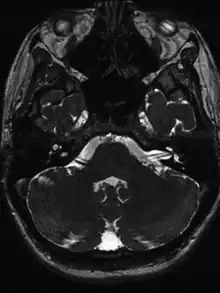

Positive head impulse test due to vestibular neuritis

Vessel loop formation on left in a individual with suspected acute vestibular neuritis

• MRI